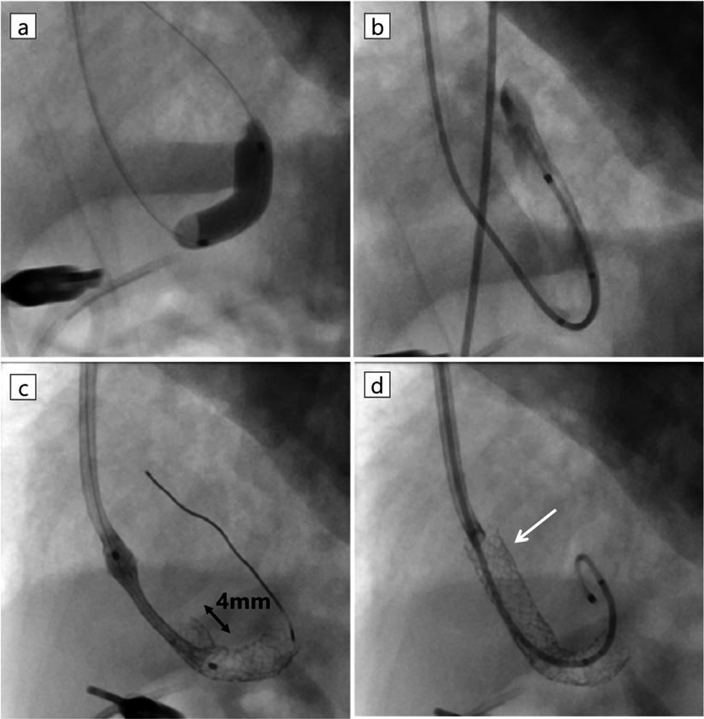

Fig. 3 Balloon dilatation and stenting for ductus venosus and vertical vein

a) Dilated by Sterling 5 mm×20 mm in the vertical vein. b) Angiogram before the procedure shows ductus venosus and vertical vein are taking a hairpin turn. c) Distal and proximal stent overlap by 4 mm. d) After the procedure. White arrow shows proximal stent protrudes into right atrium.

日齢4(修正33週2日,体重1,109 g),ミダゾラム,フェンタニル,ロクロニウムを用いた静脈麻酔薬による全身麻酔下で経皮的バルーン形成術,血管内ステント留置術を行った.肺出血の懸念があるためヘパリンは使用しなかった.臍静脈からアプロ—チした際,DV, IVCへカテーテルは挿入できるが,VVへの挿入は困難と考え,頸部からアプローチすることにした.右内頸静脈に6 Fr Merit Prelude IDealシース(Merit Medical, South Jordan, UT, USA)を留置し,4 Frマルチパーパスカテーテル(フォルテ グロウ メディカル株式会社,栃木,日本),先端転向型マイクロカテーテルである,2.9 Frレオニスムーバ®(SBカワスミ株式会社,神奈川,日本)を用いて,臍静脈カテーテルを目印にすることで0.014インチGTワイヤー®アングル(テルモ株式会社,東京,日本)をVVへ挿入できた(Fig. 2c).ガイドワイヤーの挿入が困難な場合は臍静脈カテーテルから血管造影し,臍静脈からスネアを挿入し内頸静脈から挿入したガイドワイヤーを把持して静脈管を通過させる予定であった.2.9 Frレオニスムーバ®はVVとDVがU字型に吻合している部位を通過しなかったため,1.9 Fr Carnelian® MARVEL(東海メディカルプロダクツ株式会社,愛知,日本)を使用することで,2.9 Frレオニスムーバを挿入できた.PVO解除前のカテーテル挿入,血管造影はPVO悪化による肺出血の懸念があったため,圧測定と血管造影は行わず直ちに経皮的バルーン形成術を行った.0.014インチBalance®ガイドワイヤー(Abbott, Pylmouth, MN, USA)を左肺静脈へ挿入後,血管拡張用バルーンTrek®(Abbott, Pylmouth, MN, USA)3 mm×15 mm, 4 mm×15 mmでVV,VVとDVの吻合部,DVの3か所をいずれも16気圧で前拡張した.血管拡張用バルーンSterling®(Boston Scientific, Marlborough, MA, USA)5 mm×20 mmを用い,10気圧で拡張した(Fig. 3a).VVで造影し,最狭窄部径4.7 mmと狭窄が残存していたため,ステント留置術の方針とした(Fig. 3b).

血管内ステント留置術

まずはじめに,U字型に屈曲した血管経路に対応するため,柔軟性の高い自己拡張型ステントWallstent®(Boston Scientific, Marlborough, MA, USA)6 mm×24 mmを選択した.しかし,狭窄部をデリバリーカテーテルが通過しなかったため,バルーン拡張型ステントの中でも比較的柔軟で細経であるExpress SD®(Boston Scientific, Marlborough, MA, USA)5 mm×19 mmへ変更した.6 Fr Bright-tip®ガイディングカテーテル(Cordis, Miami Lakes, FL, USA)を用い,狭窄部の通過を試みたが困難であった,そのため,NC Emerge®(Boston Scientific, Marlborough, MA, USA)5.0×15 mmを先進させ,狭窄部位を拡張しつつ,減圧と同時に同ガイディングカテーテルを追従させて狭窄部位を通過させて通過に成功した.Express SD®の遠位端がVV内,かつU字型の狭窄部分をカバーするように留置した.同規格のExpress SD® 5 mm×19 mmを先に留置したステントと4 mmオーバーラップする形でタンデムに留置した(Fig. 3c).近位側はDV全体を覆う必要があり,右房内へ突出する形態となった(Fig. 3d).2.9 Frレオニスムーバ®を用いて計測したVV内の平均圧は15 mmHgであった.手技を終了し,NICUへ挿管のまま帰室した.手技に伴う頭蓋内出血,気道出血はなかった.術後の心臓超音波検査ではステント内の血流は連続性血流だが,最大流速1.2 m/s,平均圧較差3 mmHgへ改善していた.

日齢29(修正36週6日,体重1,393 g),静脈麻酔薬による全身麻酔下でステント内再拡張を行った.右内頸静脈に5 Fr Merit Prelude IDealシースを留置し,2.9 Frレオニスムーバ®,0.016インチGTワイヤー®アングルを用いて2.9 Frレオニスムーバ®をVV内へ挿入した.計測したVV内の平均圧は30 mmHgであった.0.014インチFlexi wire(Abbott, Pylmouth, MN, USA)を挿入し,Sterling® 6 mm×20 mmで狭窄部位を10気圧で拡張した(Fig. 4a).VV内の平均圧は18 mmHgへ低下した.手技を終了し,NICUへ挿管のまま帰室した.手技に伴う頭蓋内出血,気道出血はなかった.術後の心臓超音波検査でステント内血流は連続性,最大流速1.4 m/s,平均圧較差6 mmHgであった.

Fig. 4 Balloon dilatation for in-stent stenosis

a) Dilated by Sterling 6 mm×20 mm. Because Sterling didn’t pass through the overlap area, the stents were dilated by the distal shoulder. b) Dilated by NC Emerge® 6 mm×12 mm. We used 6 Fr Bright-tip guiding catheter to deliver NC Emerge® into the stent. c) Post dilation.

治療②ではステント全体への高圧拡張が行えず,術後計測したVV圧が高いためステント内狭窄が残存していると考え予定的に2度目の再拡張を施行し,狭窄が十分に解除できなければ心内修復術を行う方針とした.

日齢38(修正38週1日,体重1,514 g),右内頸静脈に6 Fr Prelude idealシースを留置し,6 Fr Bright-tip®ガイディングカテーテルで狭窄部位を通過させ,NC Emerge® 6 mm×12 mmを用いて20気圧で拡張した(Fig. 4b, c).VV内の平均圧は16から10 mmHgへ低下した.十分な拡張が得られたと判断し手技を終了した.手技に伴う頭蓋内出血,気道出血はなかった.術後の心臓超音波検査でステント内血流は最大流速1.8 m/s,平均圧較差10 mmHgであった.